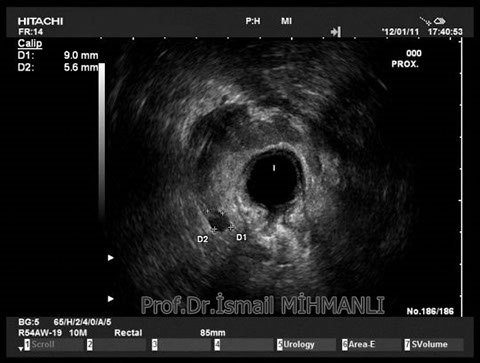

+90 212 267 35 35

PERİANAL FİSTÜLLER Perianal fistül ve abselerin intersfinkterik anal bez iltihabından kaynaklandığı düşünülmektedir. Crohn hastalarında perianal enflamatuvar hastalık sıktır. İntersfinkterik mesafedeki enfeksiyon yukarıda rektuma, aşağıda cilde, yanlarda dış sfinkteri geçerek iskiyoanal mesafeye uzanabilir. Primer fistülün sfinkterler ile ilişkisini ve abse veya sekonder dal varlığını ameliyat öncesi bilmek, tedavi planı açısından önemlidir. İskiyoanal ve iskiyorektal mesafe tutulmamışsa hastalık daha kolay tedavi edilir. Bu mesafelerde abse veya sekonder bir dal varsa fistül komplekstir ve tedavisi kompleks olmayan fistüle göre değişik olabilir. Bundan dolayı, primer fistül traktı anatomik yerleşimine göre geleneksel olarak sınıflandırılır. Bu sınıflama dörde ayrılır: 1- İntersfinkterik (iç ve dış sfinkter arasında), 2- Transsfinkterik (dış sfinkteri geçerek iskiyoanal veya iskiyorektal mesafeye ulaşmış), 3- Suprasfinkterik (intersfinkterik plandan yukarı doğru uzanan traktüs puborektal kasın Genel Gaz ve Dışkı Kaçırma (Anal İnkontinans) Perianal Fistüller Rektal Tümörler Anal Tümörler Kabızlık Yazılarımız üstündeki bir seviyeden yana kıvrılarak tekrar aşağıya iskiyoanal mesafeye uzanmış), 4- Ekstrasfinkterik (sfinkterlerin dış tarafında rektumdan direkt olarak perianal cilde uzanan traktüs). Endoanal ultrason ile hem primer fistül, hem de varsa sekonder dal ve abse doğru bir şekilde tanınır. Endoanal ultrason ile fistülün anal kanala açılan kısmını (iç uç) görmek kolaydır. Bu hastalarda sfinkter defektlerine de rastlanmaktadır. Sfinkter defekti endoanal ultrason ile kolaylıkla tespit edilir. (bkz. anal inkontinans) Perianal fistül şikayeti olan hastaların az kısmında endoanal ultrason ile bir şey görülemez ise endoanal ultrason probuna ek olarak lineer prob ile anal kanal çevresine bakmak yararlıdır. Çünkü anal kanal bileşenlerinin uzağındaki bir enflamasyon ancak bu problar ile tanınabilir.